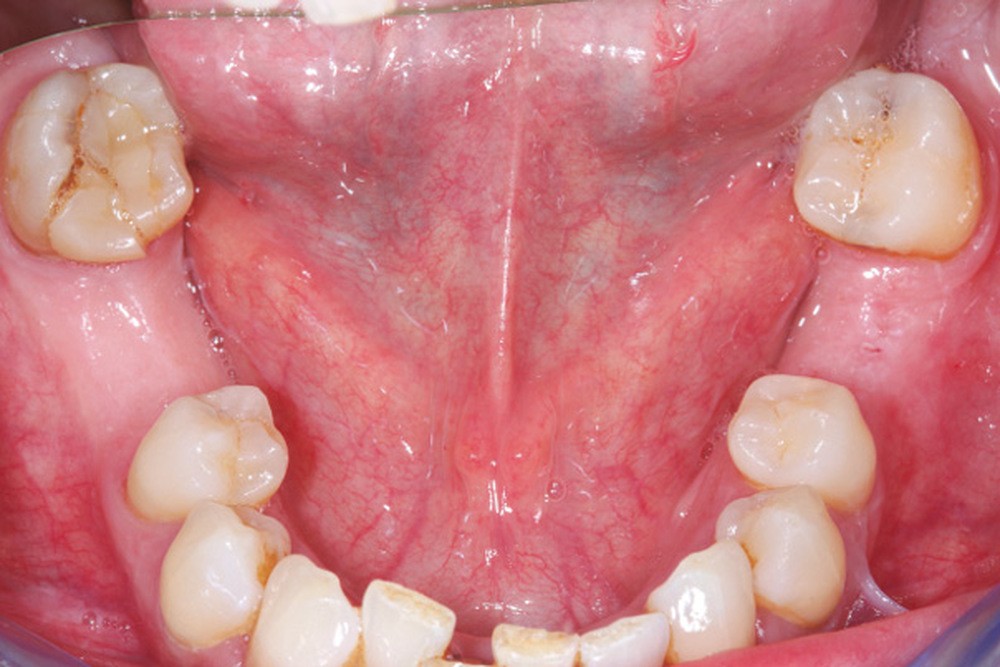

La perte d’une ou plusieurs dents entraîne la perte des points de contact, responsables de la stabilité et de la continuité de l’arcade. Par conséquent, une avulsion a pour première conséquence la migration ou la version d’une ou plusieurs dents distales (fig. 1 et 2). Cela est vrai en antérieur comme en postérieur.

Cette version, quand elle se produit, modifie les espaces interdentaires et complique l’hygiène proximale des patients. Des caries peuvent alors se développer en interproximal sans que cela soit forcément visible à l’examen visuel (fig. 3 et 4). Les radios de type bite-wing (rétro-coronaires) prennent alors tout leur sens (fig. 5 et 6).